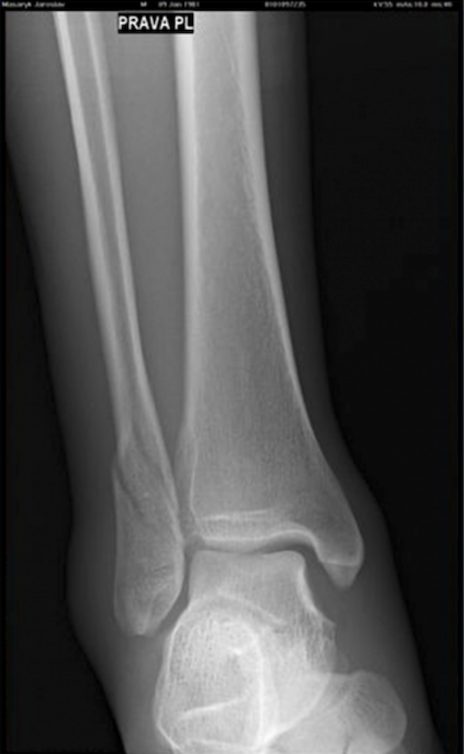

36 den od úrazu (2 snímek), rozhodnuto lékařem o vyjmutí dlahy a šroubů! (Díky urychlenému hojení pomocí Lavyl Aurica a perfektnímu stavu a srůstu kosti.)

Standardně se kovová „dlaha“ nechává navždy, ve výjimečných případech se vyndává třeba i po 6 měsících…

Aplikováno Lavyl Auricum 4x - 6x denně na ránu a 1x - 2x denně 1 střik do vody k pití.